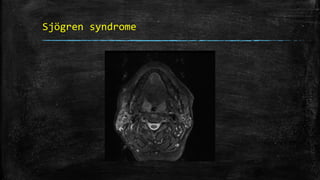

Sjögren syndrome